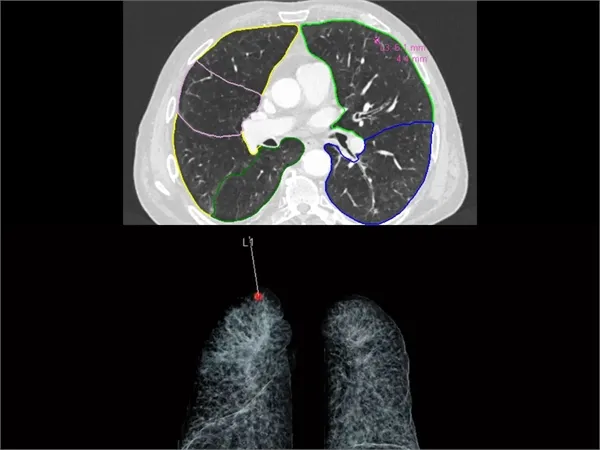

Dos imágenes muestran exploraciones pulmonares con IA. En la imagen superior, AI-Rad Companion Chest CT de Siemens Healthineers detecta y resalta nódulos pulmonares anormales. Después de la segmentación codificada por color de los nódulos pulmonares, se calculan el volumen, los diámetros y la carga tumoral. En la imagen inferior, la ubicación de un nódulo pulmonar detectado se marca con el punto rojo. Esto facilita al médico la obtención de una imagen clara de la localización del nódulo dentro del pulmón. (Crédito: Siemens Healthineers vía Klinikum Nürnberg, Nuremberg, Alemania)